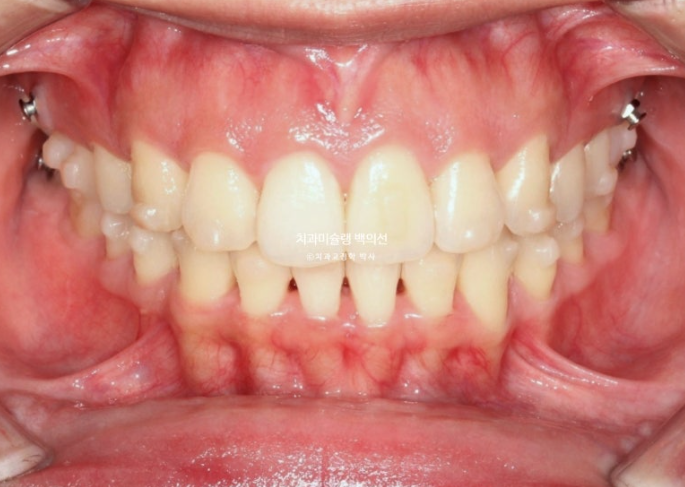

25.01

첫번째 추가장치를 모두 낀 후 모습입니다.

교합은 이미 1급 교합관계로 완성 상태입니다.

배열도 완벽합니다.

치료를 마무리 해도 되는 상황이나 환자분이 앞니 각도 개선을 좀 더 원하셔서 두번째 추가장치 제작에 들어갔습니다.

블랙트라이앵글 사이즈는 많이 줄였고 중심선은 잘 맞습니다.

어금니 교합은 물샐틈 없는 1급관계입니다.